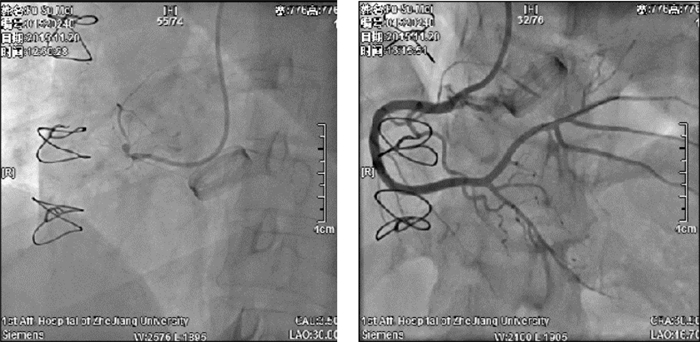

1 资料与方法患者,女,53岁,因反复胸闷、胸痛伴气短3年伴加重11 d,在当地医院治疗过程中突发晕厥,经抢救治疗3 d情况好转后转入我院。入院后完善相关检查,初步诊断:(1) 主动脉瓣关闭不全(中-重度);(2) 冠状动脉粥样硬化性心脏病,陈旧性下壁后壁心肌梗死、心功能Ⅳ级;(3)3级高血压(极高危组)。冠状动脉造影示:右冠开口处完全闭塞,可见来自左冠脉的侧枝循环。左主干正常;前降支中段30%狭窄;回旋支远段20%狭窄。升主动脉造影示:升主动脉明显扩张,主动脉瓣关闭不全。排除手术禁忌后,予2013年6月27日在全麻下行“主动脉瓣置换+右冠状动脉搭桥术(AVR+CABG术)”,手术过程顺利,术中见主动脉壁明显增厚,内膜、中层和外膜均受累,内膜增厚明显。术后予止血、抗感染、强心、利尿等治疗,查抗髓过氧化物酶抗体1.5 U/mL,抗蛋白酶3抗体1.9 U/mL,C反应蛋白(CRP)14.7 mg/L,红细胞沉降率(ESR)62 mm/h。结合患者反复左侧肢体乏力,曾伴双下肢多发痛性红斑,腹部增强CT示左侧髂总及髂内动脉血栓形成,与风湿科共同会诊,诊断为多发性大动脉炎;右冠脉闭塞;主动脉瓣关闭不全;升主动脉扩张,左侧髂总及髂内动脉血栓。治疗同时给予强的松20 mg/d,术后12 d康复出院,定期复查。2015年11月17日行冠脉CTA复查显示:冠脉搭桥术后,左主干、左前降支近端及左回旋支近端中度狭窄伴非钙化斑块形成;升主动脉瘤样扩张;未见明显桥血管。遂再次入院。入院后冠脉造影示:左主干重度狭窄;左前降支开口重度狭窄,中段可见心肌桥,收缩期轻中度狭窄;左回旋支开口及近段中重度狭窄;右冠开口闭塞;主动脉-桥血管吻合口未显影,考虑闭塞。患者拒绝再次CABG术,要求冠脉介入治疗。遂先行右冠状动脉开通(图 1),开口处植入药物涂层支架1枚,建议1个月后处理左冠状动脉,但患者未遵嘱入院再次治疗。2016年4月25日患者因“反复胸痛1月余”再次入院,入院后冠脉CTA示:右冠状动脉开口处支架植入术后改变;左主干、左前降支近端斑块形成伴重度狭窄,左回旋支近端闭塞。冠脉造影示:左主干重度狭窄;左前降支近段重度狭窄,左回旋支闭塞;右冠状动脉原支架内未见明显狭窄,可见左冠状动脉显影。建议外科二次CABG术,患者及家属要求行介入治疗,遂予左主干-左前降支药物涂层支架1枚植入并行血管内超声(IVUS)(图 2),术后3 d顺利出院。9个月后复查心脏超声示主动脉机械瓣未见明显瓣周漏,冠脉造影复查示:左前降支支架内未见明显狭窄,左回旋支闭塞,右冠支架内未见明显狭窄,右冠远端发出侧枝逆供左回旋支。患者定期门诊随访至今,病情稳定无不适症状。

| 图 1 患者右冠植入支架前后造影对比 |